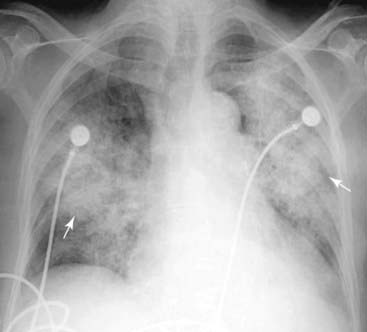

Figure 3-6 Acute pulmonary alveolar edema.

Fluffy, bilateral, perihilar airspace disease with indistinct margins, sometimes described as having a bat-wing or angel-wing configuration, is present (solid white arrows). No air bronchograms are seen. The heart is enlarged. This represents pulmonary alveolar edema secondary to congestive heart failure.